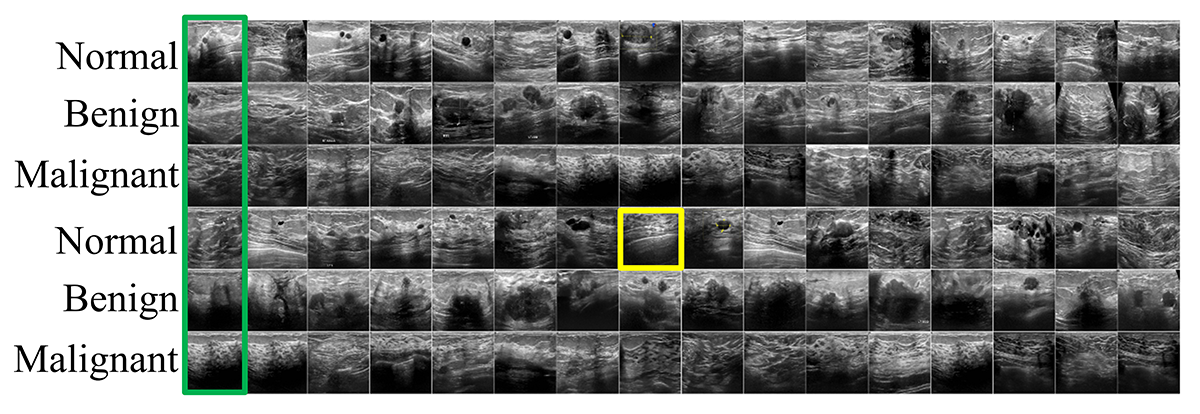

Refer to caption

(a) Busi

Figure 3: Dataset samples with their ordinal labels (category).

The Busi dataset is divided into three categories: normal, benign, and malignant images, as shown in Fig. 3 LABEL:sub@busi_data. The dataset consists of 780 images, with an average image size of 500×500500500500\times 500 pixels. For simplicity, we normalized the image size to 256×256256256256\times 256 with a range of [0,1]01[0,1]. For data augmentation, we also doubled the images by flipping them horizontally. The Finger dataset created to automatically count fingers in both the left and right hands has six categories: 0,1,2,3,4,012340,1,2,3,4,,and 555 (Fig. 3 LABEL:sub@finger_data). The data dimensions were 500×500500500500\times 500, with 18,000 and 3,600 images as the training and testing sets, respectively. We also normalized the size to 128×128128128128\times 128 pixels with an interval [0,1]01[0,1]. The FG-Net dataset is an aging database consisting of 1,002 images of various face age groups. Originally, the age range of the patients was 0–69 years. We converted them into the following groups: child (0-12 years), adolescents (13-18 years), adult (19-59 years), and senior adults (60 years and above), as depicted in Fig. 3 LABEL:sub@FG-Net_data. For data augmentation, we doubled the image using a horizontal flip. The Adience dataset is a face age recognition dataset obtained from the Flickr album. The data size 26,580 with eight categories: 0-2, 4-6, 8-13, 15-20, 25-32, 38-43, 48-53, and 60+ years old, as shown in Fig. 3 LABEL:sub@adience_data. Moreover, we conducted a pre-processing technique for both FG-Net and Adience by cropping the image centered on the face with a size of 150×150150150150\times 150 pixels and normalizing it by subtracting its mean and dividing it by its standard deviation. In this study, we randomly divided the data into five blocks (except the Adience dataset already divided into five blocks). The data were randomly split into training and testing sets of 80% and 20% for each block, respectively. Moreover, we randomly subtracted 20% of the training set for the validation set to obtain the optimum model during training. Subsequently, due to the stochastic nature of the deep learning-based model, we conducted ten repetitive experiments for each block to obtain the average and standard deviation of model performance. Furthermore, we used FaceNet [12] backbone in the embedding network of the FG-Net and Adience dataset.

To assess the accuracy of the embedding space representation, we used the K𝐾K-nearest neighbor algorithm. The K𝐾K number of similar images was obtained using a query image as the input based on the cosine similarity. We used Eq. 6 to measure the mapping accuracy of each image in the embedding space based on its label. The aijsubscriptsuperscript𝑎𝑗𝑖a^{j}_{i} corresponds to the correctness between the label of the query image (lisubscript𝑙𝑖{l}_{i}) and the neighbor image label (l^jsubscript^𝑙𝑗{\hat{l}}_{j}); where its value is 1, when the label is the same; otherwise, 0. The K𝐾K nearest neighbor performance of each model is shown in Fig. 4. In the Busi, FG-Net, and Adience datasets, the results reveal that, generally, our proposed model outperforms existing DML models. The S𝑆S-Net is trained based on a binary-like classification, where it is devised to distinguish between the inner and outer categories. Therefore, the performance may be less accurate than that of our O𝑂O-Net, which is explicitly trained to simultaneously distinguish the inner, outer, and ordinal relationships among the categories. Furthermore, defining the anchor, positive, and negative samples in T𝑇T-Net is crucial. The distance between the anchor and the positive samples should be shorter than that of the negative sample. Thus, its performance on the Busi dataset was not significantly accurate. Note that the samples of each category (normal, benign, and malignant) in the Busi dataset have similar features (Fig. 3 LABEL:sub@busi_data), making them difficult to distinguish with a triplet loss. Meanwhile, in the FG-Net and Adience datasets, T𝑇T-Net has better accuracy than the Busi dataset because it uses a pre-trained network (FaceNet) as a backbone in the embedding network. Q𝑄Q-Net outperformed O𝑂O-Net when the K=10𝐾10K=10 in the Adience dataset. However, with increasing K𝐾K, the accuracy was competitive. Because the number of batches significantly influences the N𝑁N-Net accuracy, we employed two types of N𝑁N-Net, namely, N𝑁N-Net1 and N𝑁N-Net2. The difference between N𝑁N-Net1 and N𝑁N-Net2 is the number of batches used during the training. N𝑁N-Net1 used the same number of batches as the other networks. For comparison, N𝑁N-Net2 was set to use a huge batch size (1,000). As shown in Fig. 4, the higher the number of batches in N𝑁N-Net, the higher its accuracy. Moreover, a fascinating finding in the Finger dataset is that all models have perfect accuracy because the separability of this data is very high, as shown in Fig. 3 LABEL:sub@finger_data.